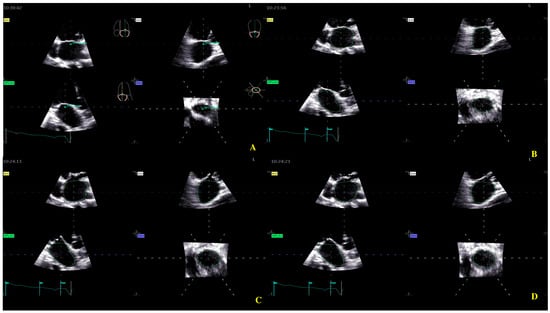

Four-dimensional echocardiograms were acquired using live 4D imaging in AF patients and electrocardiographically (ECG)-gated 4DE acquisition for SR patients. In live 4D imaging, a volumetric data set of a relatively narrow pyramidal sector is acquired and displayed in RT. In ECG, multiple-beat acquisition volumes are stitched together during four consecutive heart cycles during a single-breath hold. The minimum volume rate for LA 4DE strain measurements was 25 volumes per second (VPS) (Figure 1A); for MV 4DE measurements, it was 16 volumes per second (Figure 1B). Care had been taken regarding the volume rate because, as previously shown, a low temporal resolution might lead to an underestimation of strain magnitude [16,17,18].

Figure 1.

Four-dimensional transthoracic echocardiography (4D TTE) acquisition: (A) LA multi-slice acquisition; (B) MA multi-slice acquisition.